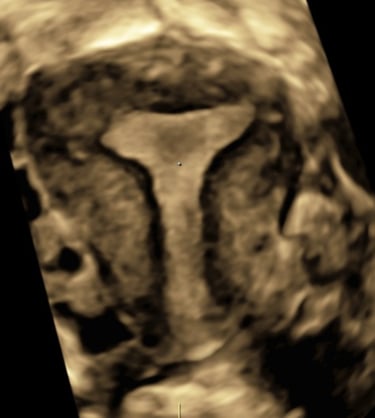

L’échographie du 3ème trimestre (photo 3D)

L’échographie du 3ème trimestre doit être réalisée entre 31 SA et 34 SA. Elle permet de réaliser un dernier examen morphologique, de préciser la croissance du fœtus, la localisation placentaire et la quantité de liquide amniotique.